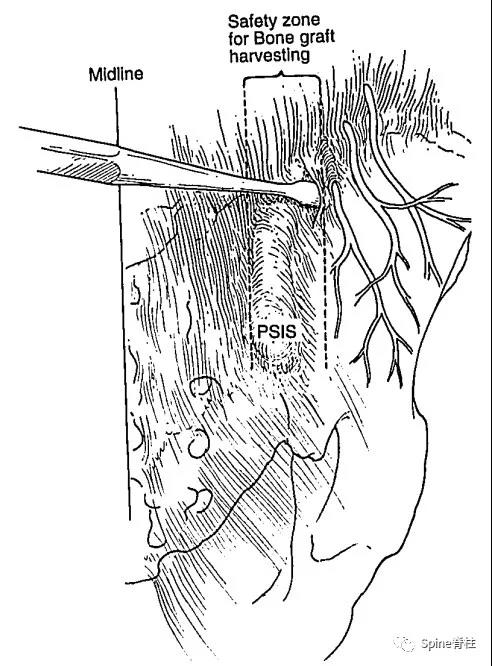

臀上皮神经卡压综合征患者主要表现为臀上皮神经支配区(臀上部)的疼痛、麻木和感觉减退。有研究发现,传统切口取髂骨自体骨移植时,其切口平行于后髂嵴,位于髂嵴上方,并从髂后上棘向外侧延伸,容易导致臀上皮神经的损伤,从而出现与臀上皮神经卡压综合征类似的症状和体征,即臀上部疼痛、麻木不适,部分人会有烧灼样感觉过敏。而采用改良切口垂直于髂嵴,并与臀上皮神经纵向平行,则减少了上述症状的发生。

图:虚线处为安全取骨区